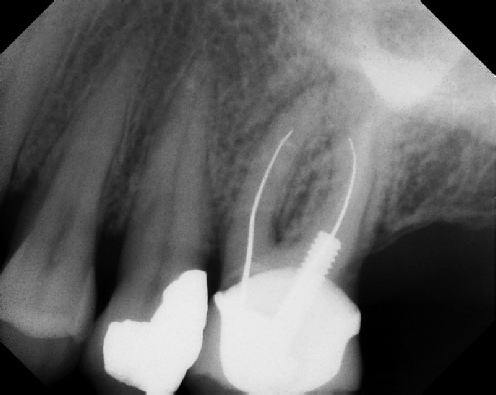

Root Canal Retreatment - Meriden 8 mos. recall Post-op Pre-op